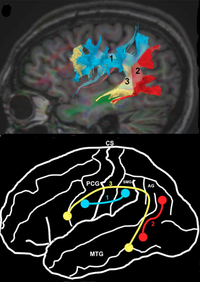

Hjernens cortex opdeles i Gyri og Sulci, hvor ca. 70% af cortex er lokaliseret i sulci, altså ikke umiddelbart synlig når man kigger på hjernens overflade. Lokalisering og udformning af sulci er ganske variable på nær enkelte sulci (lateral fissuren, Fissura interhemispherica, Sulcus Centralis, Sulcus Cinguli og Sulcus Parietooccipitalis) dette ses fint illustreret i Fig.1 hvor der er lavet fusion af MR-skanninger fra XX personer. Man kan se af de fleste sulci og gyri bliver "midlet ud" fordi de har variable lokalisation, mens nogle enkelte tydeligt træder frem, fordi de har en relativt konstant placering.